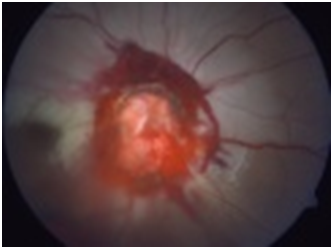

A 15-year-old healthy male presented with an ocular injury sustained while playing basketball. He described a finger poke incident with the contact made with the lower aspect of his right eye. Immediately following the injury, he described loss of vision of the right eye. On presentation to the emergency eye clinic 2 hours later, his visual acuity was no light perception in the right eye. A right relative afferent pupillary defect was present. A conjunctival tear and associated chemosis was present in the inferior bulbar conjunctiva. A micro-hyphaema with 2+ red cells was found in the anterior chamber but the cornea, lens and intraocular pressure were all normal. Examination of the posterior segment revealed localized vitreous haemorrhage arising from the disc. The disc itself appeared disorganized and recessed behind the globe with an obvious defect in the disc superiorly (Figure 1). Gentle palpation of the globe during fundus examination showed that some streaks of vitreous haemorrhage adjacent to the disc were mobile and could pass through the disc defect with gentle palpation and return into view on release of palpation. There was retinal pallor affecting the superior temporal and nasal aspects of the retina (Figure 2). A B-Scan ultrasound demonstrated alteration in the normal contour of the optic nerve/ globe junction and hypo echogenic area adjacent to the nerve (Figure 3). MRI of the brain and orbit showed disruption in the area of lamina cribrosa of the right eye (Figure 4). At 3 weeks following the injury, progressive dense vitreous haemorrhage prevented visualization of the posterior pole (Figure 5). Subsequent follow up after one month showed that the vitreous haemorhage disperse spontaneously, with persistent optic nerve disorganization and no improvement in vision.

Figure 1 Fundus picture showing Optic Nerve Avulsion.